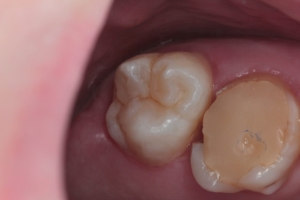

Приклади робіт лікаря-стоматолога

Естетична реставрація. До / після